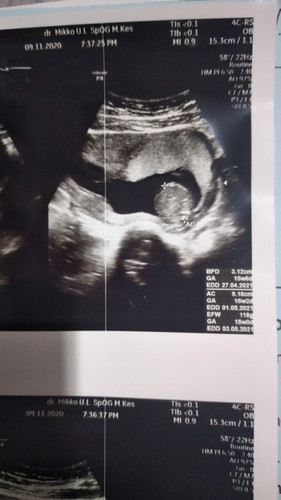

Perkiraan melahirkan saya kira2 yang mana ya bun? EDD nya ada 3 diketerangan. Mohon bantu.

hai bun, sebelumnya salam kenal ya. semoga jawaban saya bisa sedikit membantu. kalau dilihat dari hasil usg nya : EDD 1 didapatkan dari ukuran tulang pelipis kedua sisi janin. EDD 2 didapatkan ukuran lingkar perut janin EDD 3 didapatkan dari berat bdn janin. jadi kesimpulannya bunda berpatokan pada hasil sekitar tanggal 27 april - 3 mei ade bayi perkiraan sangat siap untuk lahir. akan tetapi ada kemungkinan bisa maju atau mundur juga ya bun ๐. terima kasih